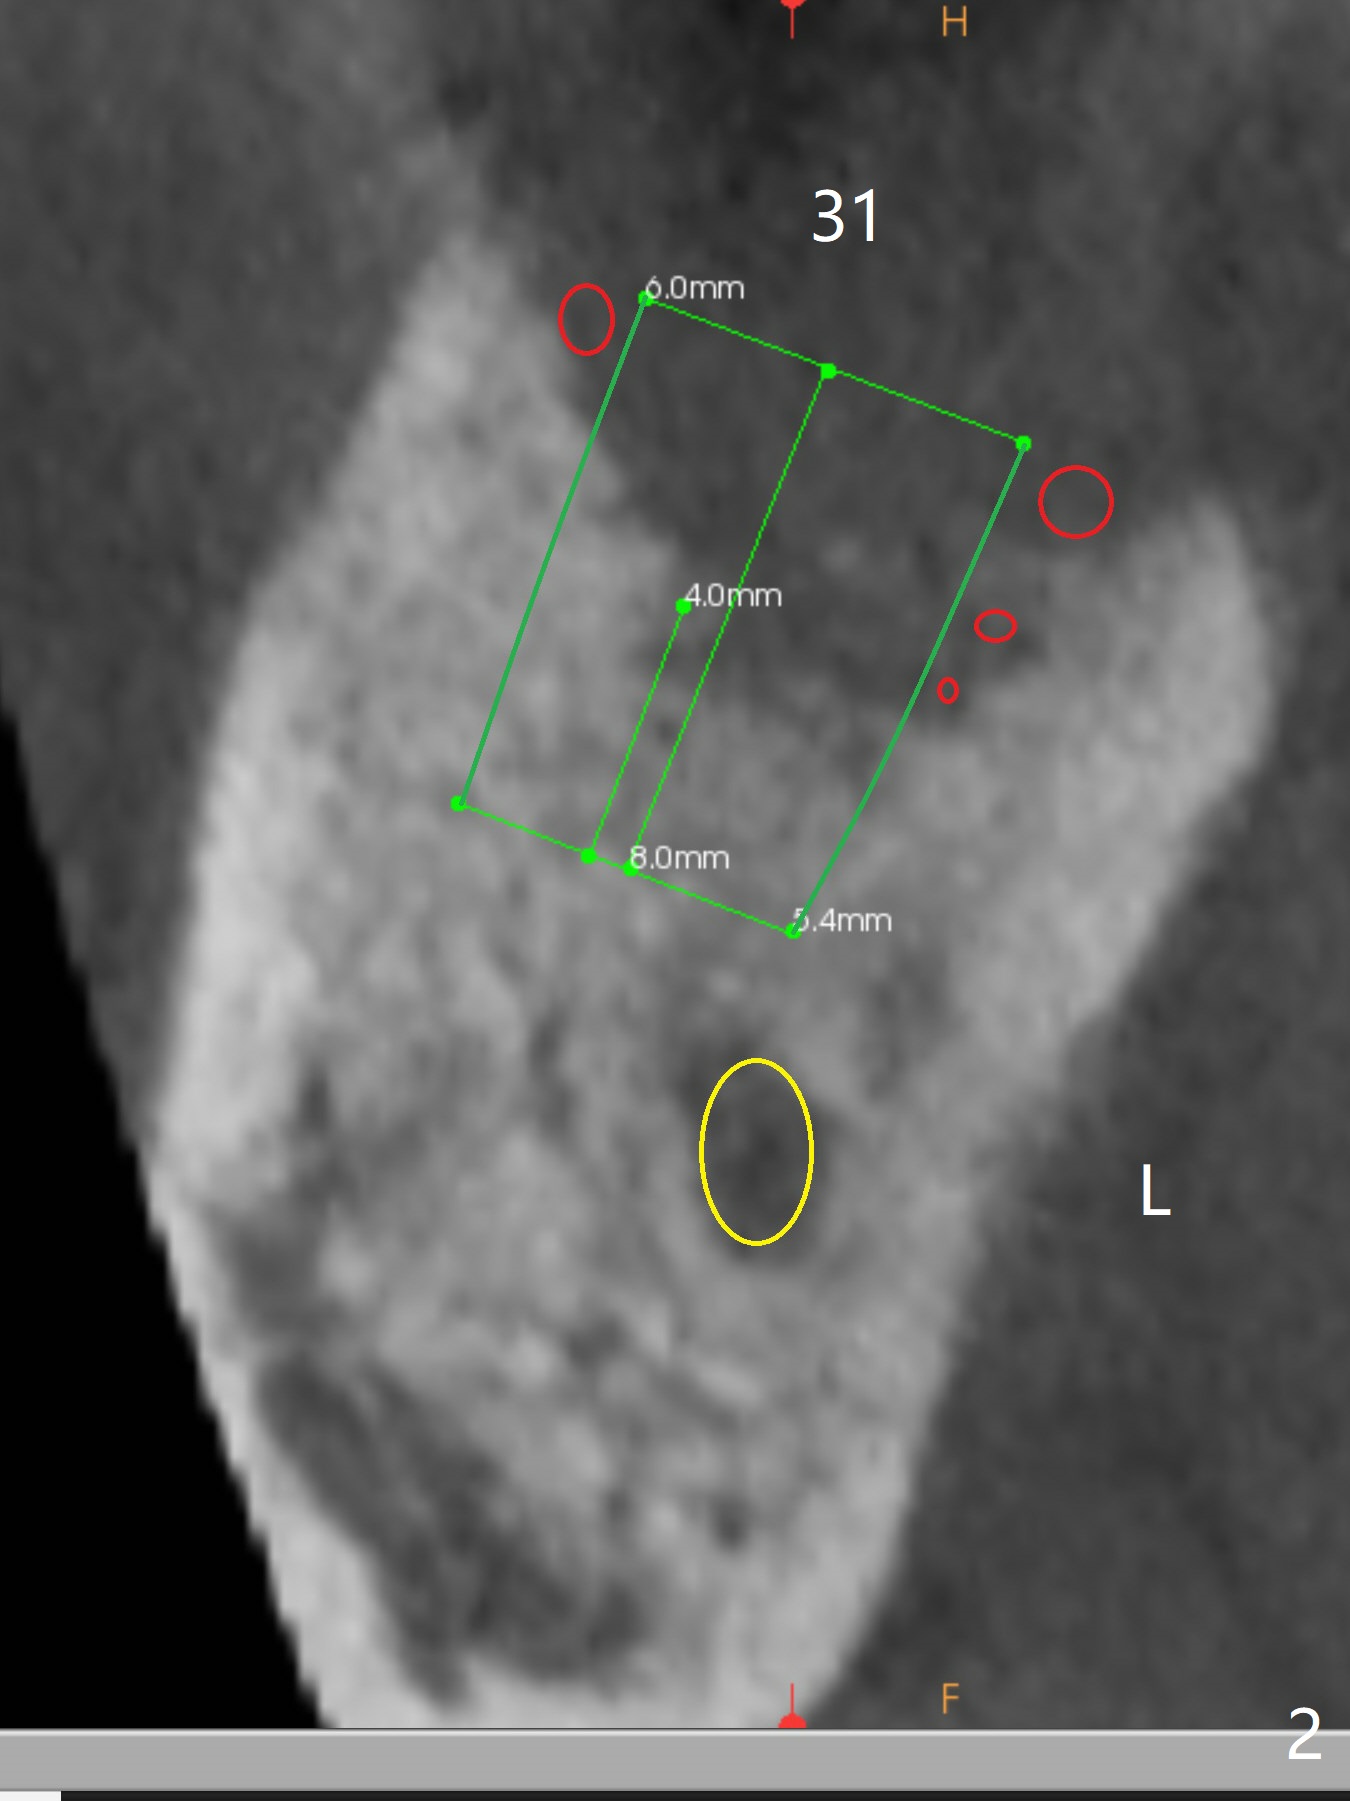

After having upper implants placed (9-11, 15 UR), a 46-year-old man requests taking care of the loose tooth at #31 and the missing tooth #28 next (Fig.1). Bone height is limited at #31 (Fig.2); if hemorrhage and pain are controllable, an extra wide Bicon implant will be placed. In the posterior region with unfavorable implant crown ratio, there is less likelihood to separate Bicon abutment from its implant because of friction mechanism. But 3-5 mm stoppers and drills are from another implant system (regular and wide kits). CT may be taken intraop if needed. PRF membranes will be used to close the large socket opening with a hole for abutment penetration if instructed. Autoclave a needle with endo syringe to inject PRF liquid into the tissue to facilitate tissue healing.